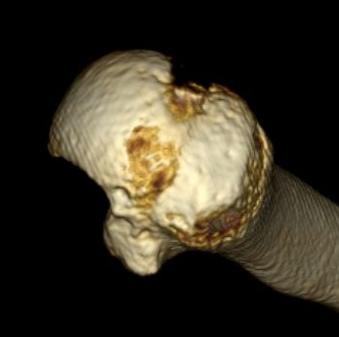

Reverse Hill Sachs

Humeral head defect

- caused by impaction of anterior humeral head on posterior glenoid

- intra-articular

- measured as a percentage of the articular surface

Osteochondral Allograft Reconstruction

Indication

Reverse Hills Sachs defects 25 - 50%